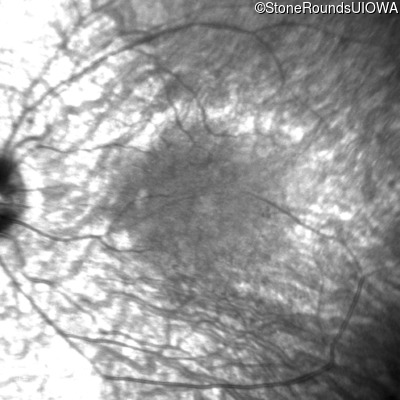

Infrared Fundus Photograph - Left - 20/40

Exemplar